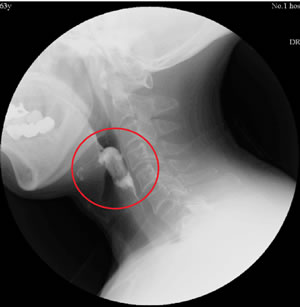

治疗前吞咽造影显示食物大量残留在梨状窦 治疗后吞咽造影显示食物已全部咽下,未见

及喉腔,环咽肌不开放 明显残留